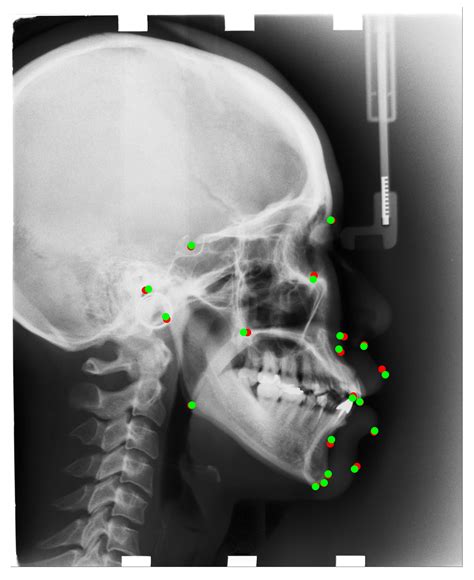

Interpreting a Cephalometric X Ray requires a thorough understanding of craniofacial anatomy and orthodontic principles. The orthodontist analyzes various landmarks and measurements to assess the patient’s dental and skeletal relationships. Some of the key landmarks and measurements include:

Key Landmarks

The following table outlines some of the key landmarks used in Cephalometric X Ray analysis:

Landmark Description

Sella (S) The center of the sella turcica, a depression in the sphenoid bone

Nasion (N) The most anterior point of the frontal bone at the nasofrontal suture

Orbitale (Or) The lowest point on the inferior margin of the orbit

Pogonion (Pog) The most anterior point on the chin

Gnathion (Gn) The most inferior point on the symphysis menti

Key Measurements

Artificial Intelligence

Artificial intelligence (AI) has the potential to revolutionize Cephalometric imaging by automating the analysis of X-ray images. AI algorithms can identify landmarks and measurements with high accuracy, reducing the potential for human error and improving the efficiency of the diagnostic process.